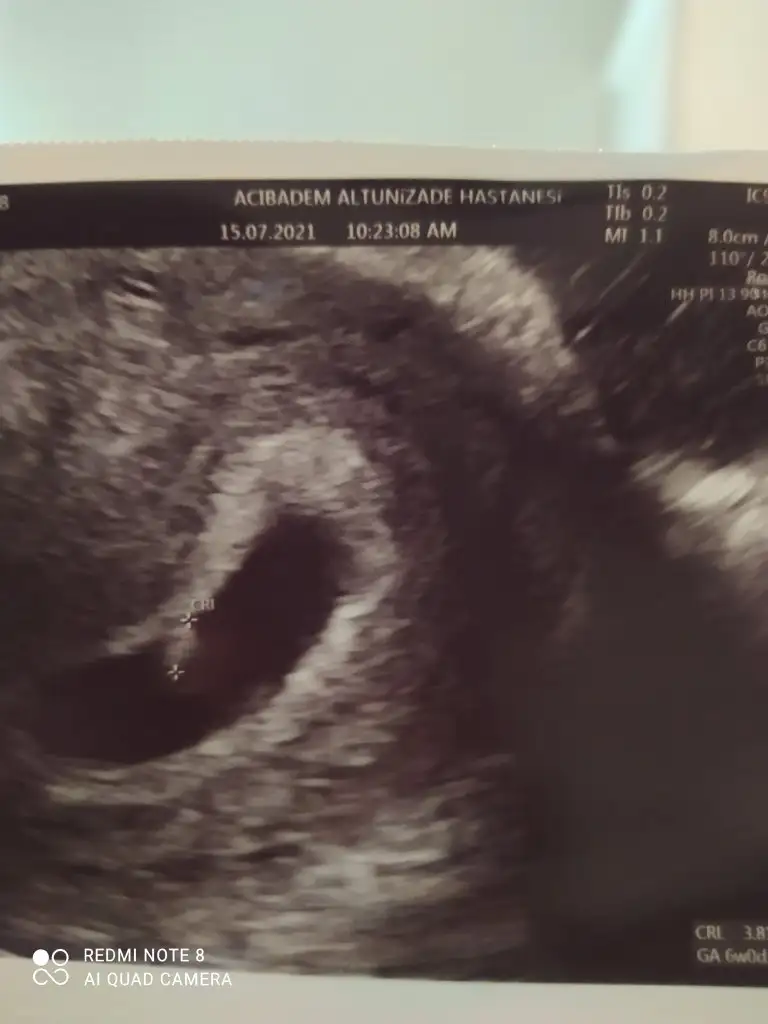

Merhaba canım dün sabah gittim ilk karından bakıldı. Kese ve içinde embriyo gözüktü çok şükür ama minik olduğu için kalp atışı duyulmadı.alttan bakalimmi dedi doktor baktık çok şükür derinden de olsa duyuldu duyulmasindan ziyade ekranda ufacık kalbi pırpır ediodu onu gördüm çok şükürMerhaba ,